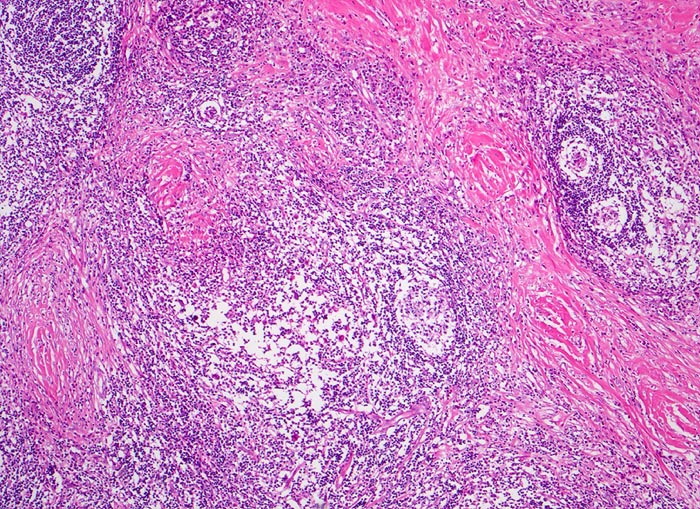

Hodgkin-Lymphom, noduläre Sklerose

Zerstörung der regulären Zonierung und Gliederung des Lymphknotens durch bindegewebig abgegrenzte Noduli, die aus einem unterschiedlich zellreichen bunten Infiltrat bestehen.

Die noduläre Sklerose ist ein Subtyp des klassischen Morbus Hodgkin mit Kollagenbändern, die mindestens einen Knoten lymphatischen Gewebes umschliessen. Diese enthalten Hodgkin- und Reed-Sternberg Zellen in Form von Lakunarzellen.